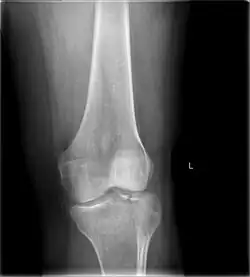

Tibial plateau fracture

![]() | |

| A severe tibial plateau fracture with an associated fibular head fracture | |

A tibial plateau fracture is a break of the upper part of the tibia (shinbone) that involves the knee joint.[1] This could involve the medial, lateral, central, or bicondylar (medial and lateral).[3] Symptoms include pain, swelling, and a decreased ability to move the knee.[1] People are generally unable to walk.[2] Complication may include injury to the artery or nerve, arthritis, and compartment syndrome.[1]